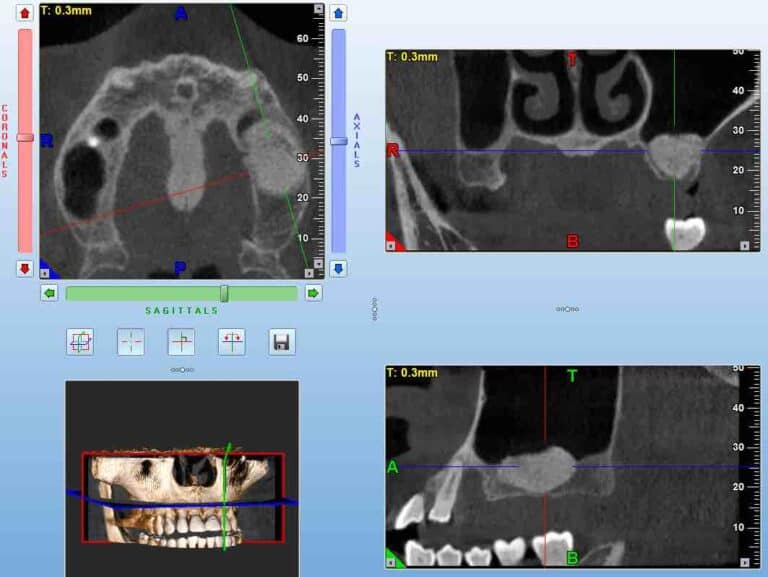

The DASRA Challenge, free online:

Study the anatomy

use detailed slices from CBCT data of a specific location

Synthesize

Combine different slices and views

Reconstruct

Find the configuration of the missing part from a list f available options

An important question for everyone. Do not mix SRA with other surgical skills such as cutting and suturing, SRA is an underlying skill. It will “naturally” grow with every surgery, but if you want to excel it you have to target it with specific training, just like anything else. And if you want to test your level, you also need some specific test. Many tests are available to test SRA, most of them are very generic though. Some time ago with Dr. James Chow and Dr. Coral Yao we developed a test specific to understanding surgical anatomy with the use of CBCT. The challenge here is to reconstruct a 3Dimensional anatomic space from 3 2D representations, as we routinely have to do while “reading” a CBCT. The test was called DASRA and was scientifically validated. It will give you an idea of the level of an important skill for implant surgery and it’s available online for free. Take the DASRA challenge and remember to leave us your thoughts and comments.